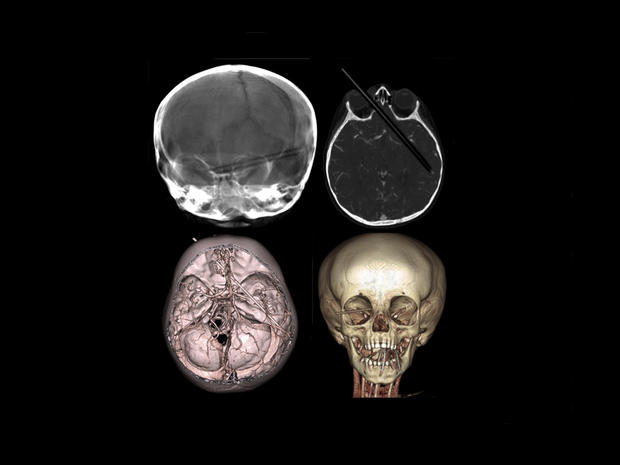

This tomography scan released Thursday, Aug. 16, 2012 by the Miguel Couto hospital, shows the skull of 24-year-old construction worker Eduardo Leite after it was pierced by a metal bar in Rio de Janeiro, Brazil. Doctors say Leite survived after a 6-foot metal bar fell from above him and pierced his head. Doctor's reportedly successfully withdrew the iron bar during a five-hour-long surgery.